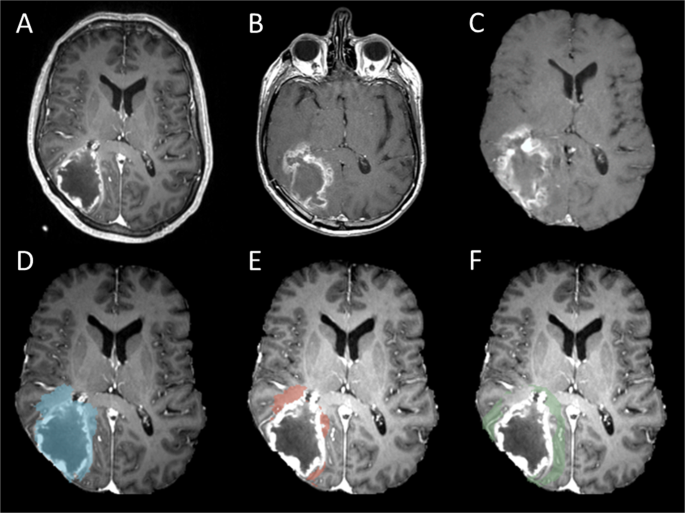

Two main regions of interest (ROIs), progression areas and non-progression areas were created in this study (Fig. 1).

All patients had radiological tumour progression in our cohort. The progression area was drawn from the first tumour progression T1 contrast MRI (Fig. 1B) according to the RANO criteria20 by the first authors (J.L.Y.) and approved by the 3rd author (A.H.). In order to avoid pseudoprogression, we examined at least two follow-up scans after the first radiological tumor progression, except for a few patients with rapidly clinical deterioration, and did not receive another follow up scan after the progression.

The areas of the tumour progression (Fig. 1C,D) were created by coregistration the progression contrast enhanced T1 MRI (Fig. 1B) to the pre-operative diagnostic MRI (Fig. 1A). This was done by using a previous described two stage non-linear semi-automatic coregistration21. In short, firstly, we calculated the transformation matrix between preoperative tumour and postsurgical resection cavity by using the linear FLIRT co-registration. Then we applied this transformation matrix to a non-linear FNIRT transformation to coregister the brain. After subtraction of the preoperative contrast enhanced lesion, the peritumoural tumour progression (Fig. 1E) and non-progression areas (Fig. 1F) can be identified on the preoperative MRIs.

The non-progression areas were created from the peritumoural 5, 10, 15, 20 mm excluding the progression areas. In addition, a contralateral area of normal appearing with matter (NAWM) as control representing normal brain tissue.